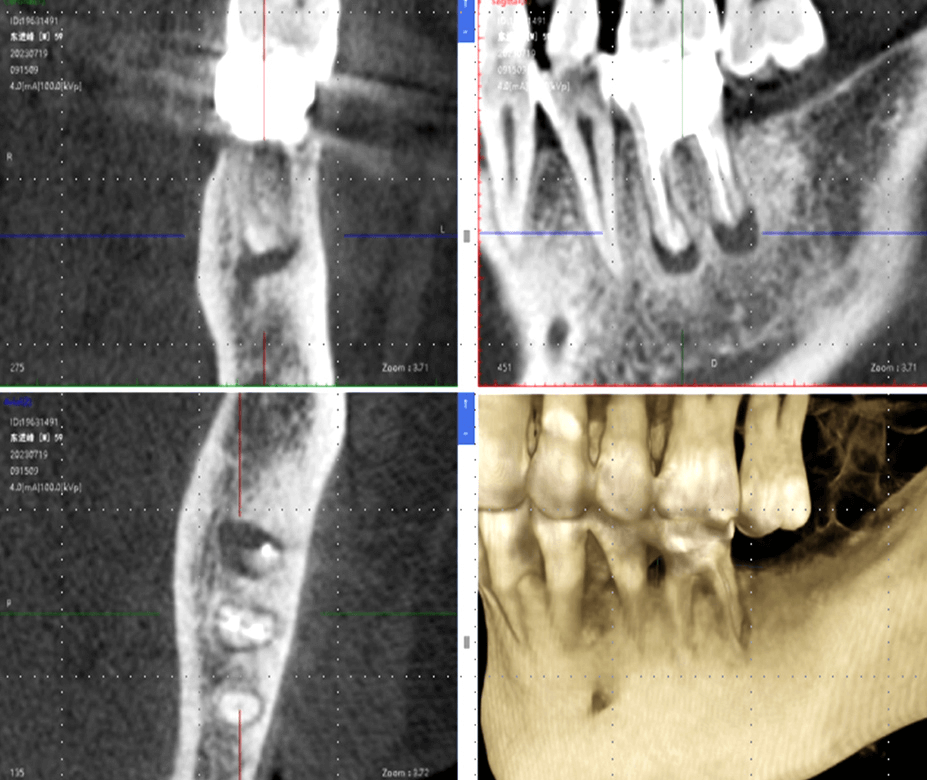

CBCT inicial + digitalização intraoral

Adaptação a diferentes dados de CBCT e digitalização intraoral; tratamento numa única visita, planeamento imediato; cirurgia no mesmo dia / prótese no mesmo dia

Registo Secundário de Pontos e Nuvem

Integração precisa entre modelos virtuais e estruturas reais